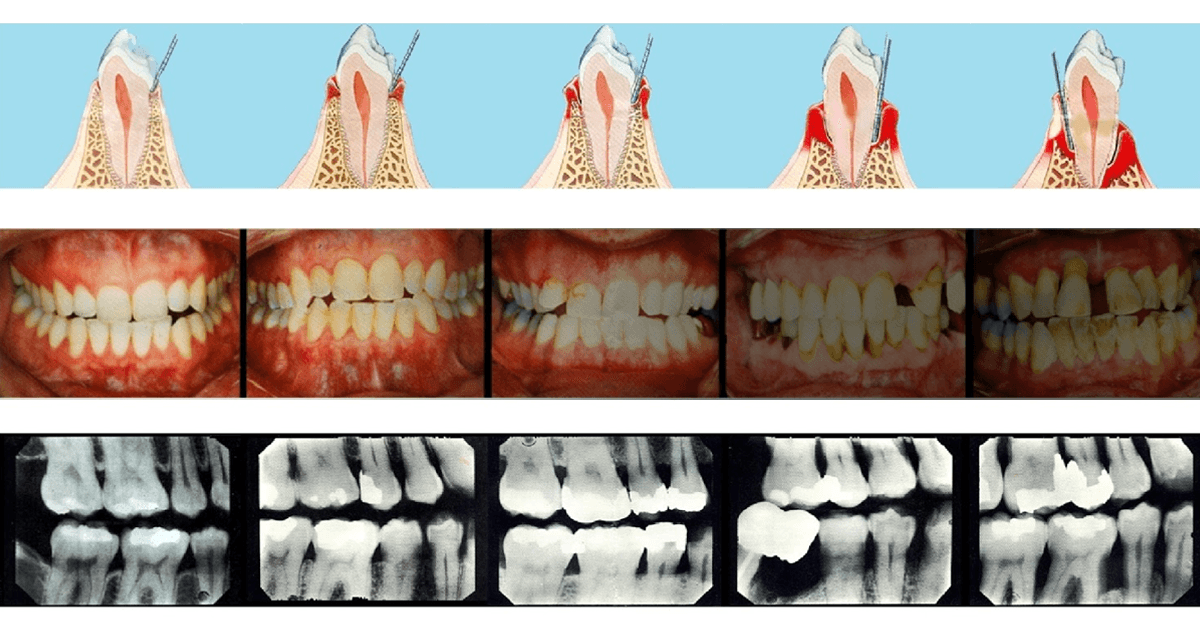

Jau 1960 metais buvo nustatyta, kad periodontas labiausiai kenčia dėl susikaupusių apnašų. Žmogaus burnoje galima aptikti maždaug šeši šimtus rūšių bakterijų: dalis jų neturi neigiamo poveikio sveikatai, tačiau kai kurios bakterijos gali sukelti įvairius negalavimus. Jei nesirūpinama tinkama dantų ir dantenų higiena, ima kauptis apnašos, iš kurių vėliau susiformuoja dantų akmenys. Nors patys dantų akmenys nesukelia periodonto ligų, tačiau jų šiurkšti ir porėta tekstūra sudaro palankesnes sąlygas kauptis bakteriniam apnašui. Ilgainiui tarp dantų ir dantenų atsiranda tarpeliai, kurie vadinami dantenų kišenėmis. Atsiradus šiai patologijai bakterijos ima dar sparčiau daugintis, todėl išsivysto uždegimas, apimantis gilesnius audinius ir žandikaulio kaulą. Ligos eigai įtakos turi imuninė sistema – jei periodontitas nėra laiku gydomas, šis susirgimas didina širdies susirgimų riziką, gali neigiamai paveikti diabeto eigą ar lemti priešlaikinį gimdymą.

Periodontologas visada vertina paciento burnos būklę ir sudaro individualų gydymo planą. Jei nėra diagnozuojami negrįžtami pakitimai, kartais tereikia atlikti profesionalią burnos higieną ir nuvalyti viršdanteninius ir podanteninius akmenis. Jei procesas pažengęs atleikamas giluminis valymas (dantenų kiuretažas) su uždegimo pažeistų dantenų konservatyviu pašalinimu. Ypatingai sunkiais atvejais atliekama atliekama lopo operacija, kai pašalinamas didelis kiekis pažeistų dantenų, žandikaulio defektai gali būti užpildomi kaulo užpildais. Šiuolaikinė periodontologija užtikrina, kad pacientui atliekamos procedūros nesukels pernelyg didelio diskomforto – visuomet yra taikomas nuskausminimas.